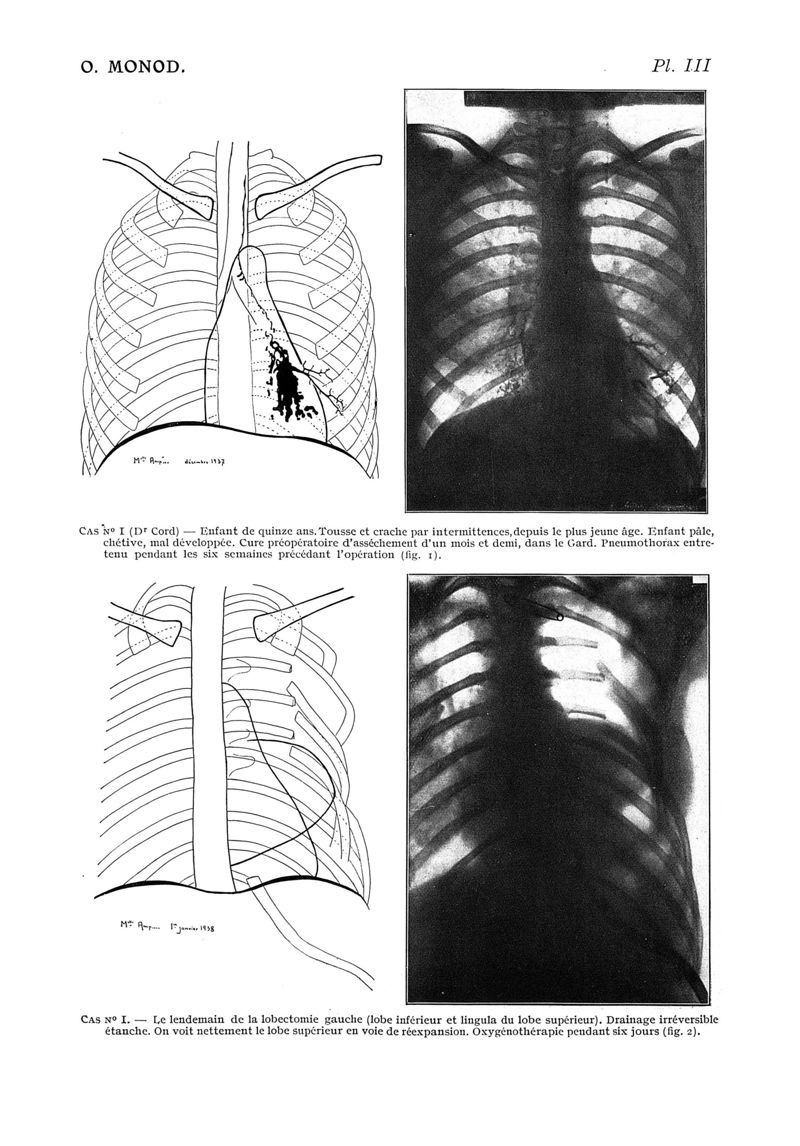

Paris médical : la semaine du clinicien

1939, n° 111, partie médicale. - Paris : J.-B. Baillière et fils, 1939.